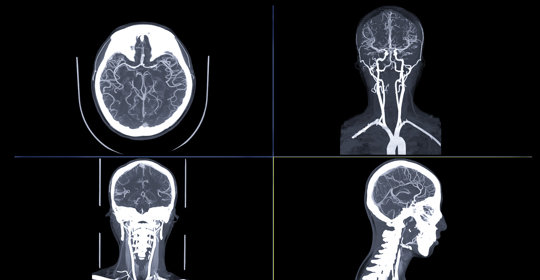

計算機斷層掃描血管造影術

CTA是透過注射含碘顯影劑後拍攝多層面影象以觀察血管分佈狀況的一種影像學檢查手段。對於主動脈剝離而言,CTA能夠提供詳細的解剖資訊,並幫助識別可能存在的異常如假腔或內膜撕裂等。

CTA是採用高壓注射器快速注入含碘顯影劑後再行CT掃描的方法,在X光照射下獲取受檢部位的二維投影資料,並重建得到各種橫截面影象。患者仰臥於檢查床上,根據指示調整姿勢以便更好地對目標區域進行成像。